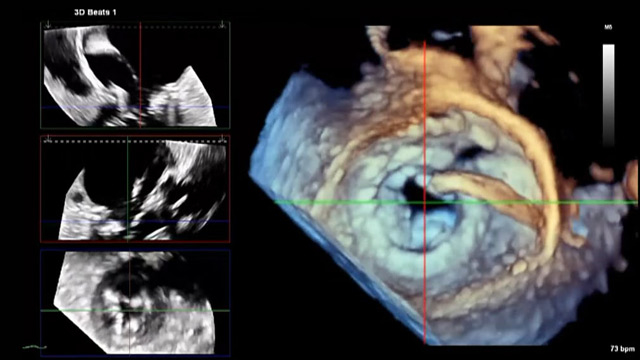

Procedural imaging for tricuspid valve interventions

16 Nov 2025 – From PCR London Valves 2025

Master procedural imaging techniques essential for tricuspid valve interventions, including TOE views, multi-phase reconstruction, and 3D/4D steering. This session also covers quantification of residual tricuspid regurgitation post-device deployment and the appropriate use of intracardiac echocardiography.